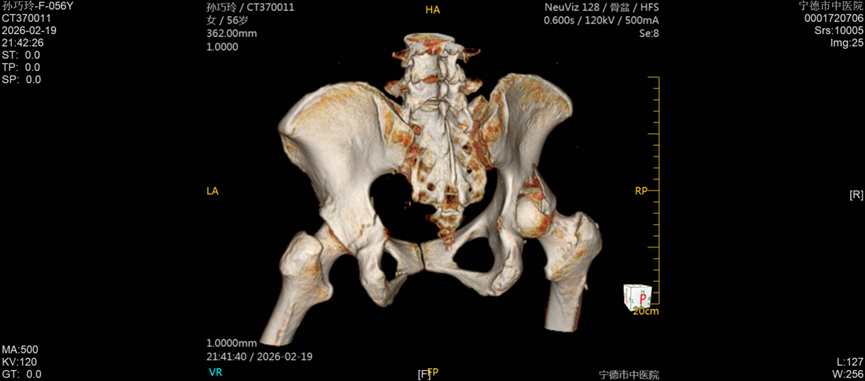

今年57岁的孙女士,因车祸外伤被紧急送往宁德市中医院创伤骨科就诊,经检查确诊为右侧髋臼后壁骨折伴股骨头后脱位,左侧髋臼T形骨折且累及四边体。据了解,髋臼骨折多由高能量损伤引发,其解剖结构复杂,毗邻重要血管神经,复位精度要求高、手术风险大,一直是创伤骨科领域的高难度手术,而双侧髋臼骨折更是该领域中极具挑战性的病例,不仅创伤重、术中出血风险高,诊疗难度也大幅提升。更为棘手的是,孙女士还合并有严重糖尿病及Ⅰ型呼吸衰竭,这无疑进一步增加了病情的复杂性和诊疗的艰巨性。